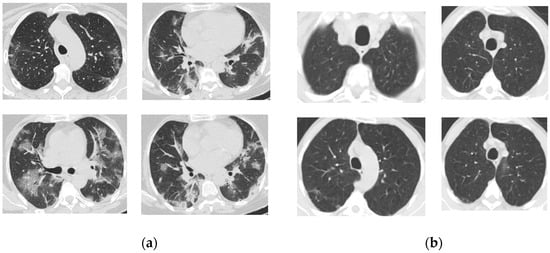

We validate the proposed approach by employing a publicly accessible repository of SARS-CoV-2 CT scan images. The dataset, available on Kaggle, has a total of 2482 CT scans, each taken from a single patient, containing 1252 CT scans that are positive for SARS-CoV-2 infection and 1230 CT scans for patients not affected by SARS-CoV-2. The whole dataset is reported to be collected from real patients in hospitals from Sao Paulo, Brazil [32,33,34]. Figure 1 exhibits a selection of CT scan images depicting both COVID-19 and non-COVID-19 instances.

Figure 1. (a) COVID-19 and (b) non-COVID-19 samples [32].